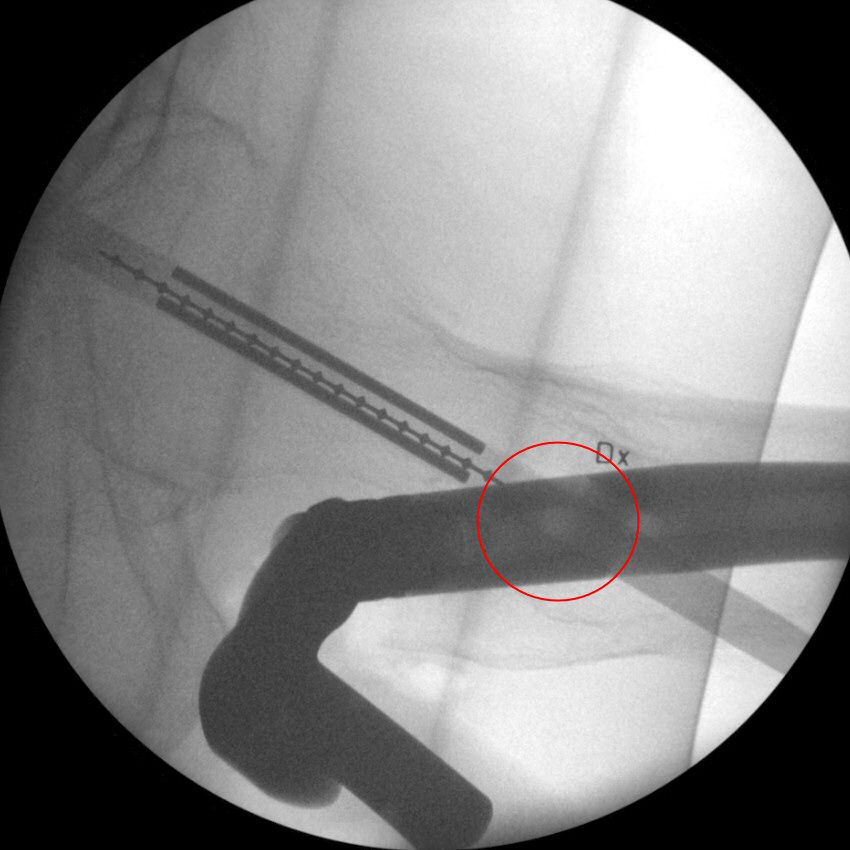

- Vrid mallen ca 90°. Titta i sidovy. Vrid spiken och justera mallen så den passerar märgspikena hål för glidskruven och hamnar motsvarande centralt i kollum och kaput.

Sidobild, mall i genomlysning, märgspikens glidskruvshål markerat med röd cirkel